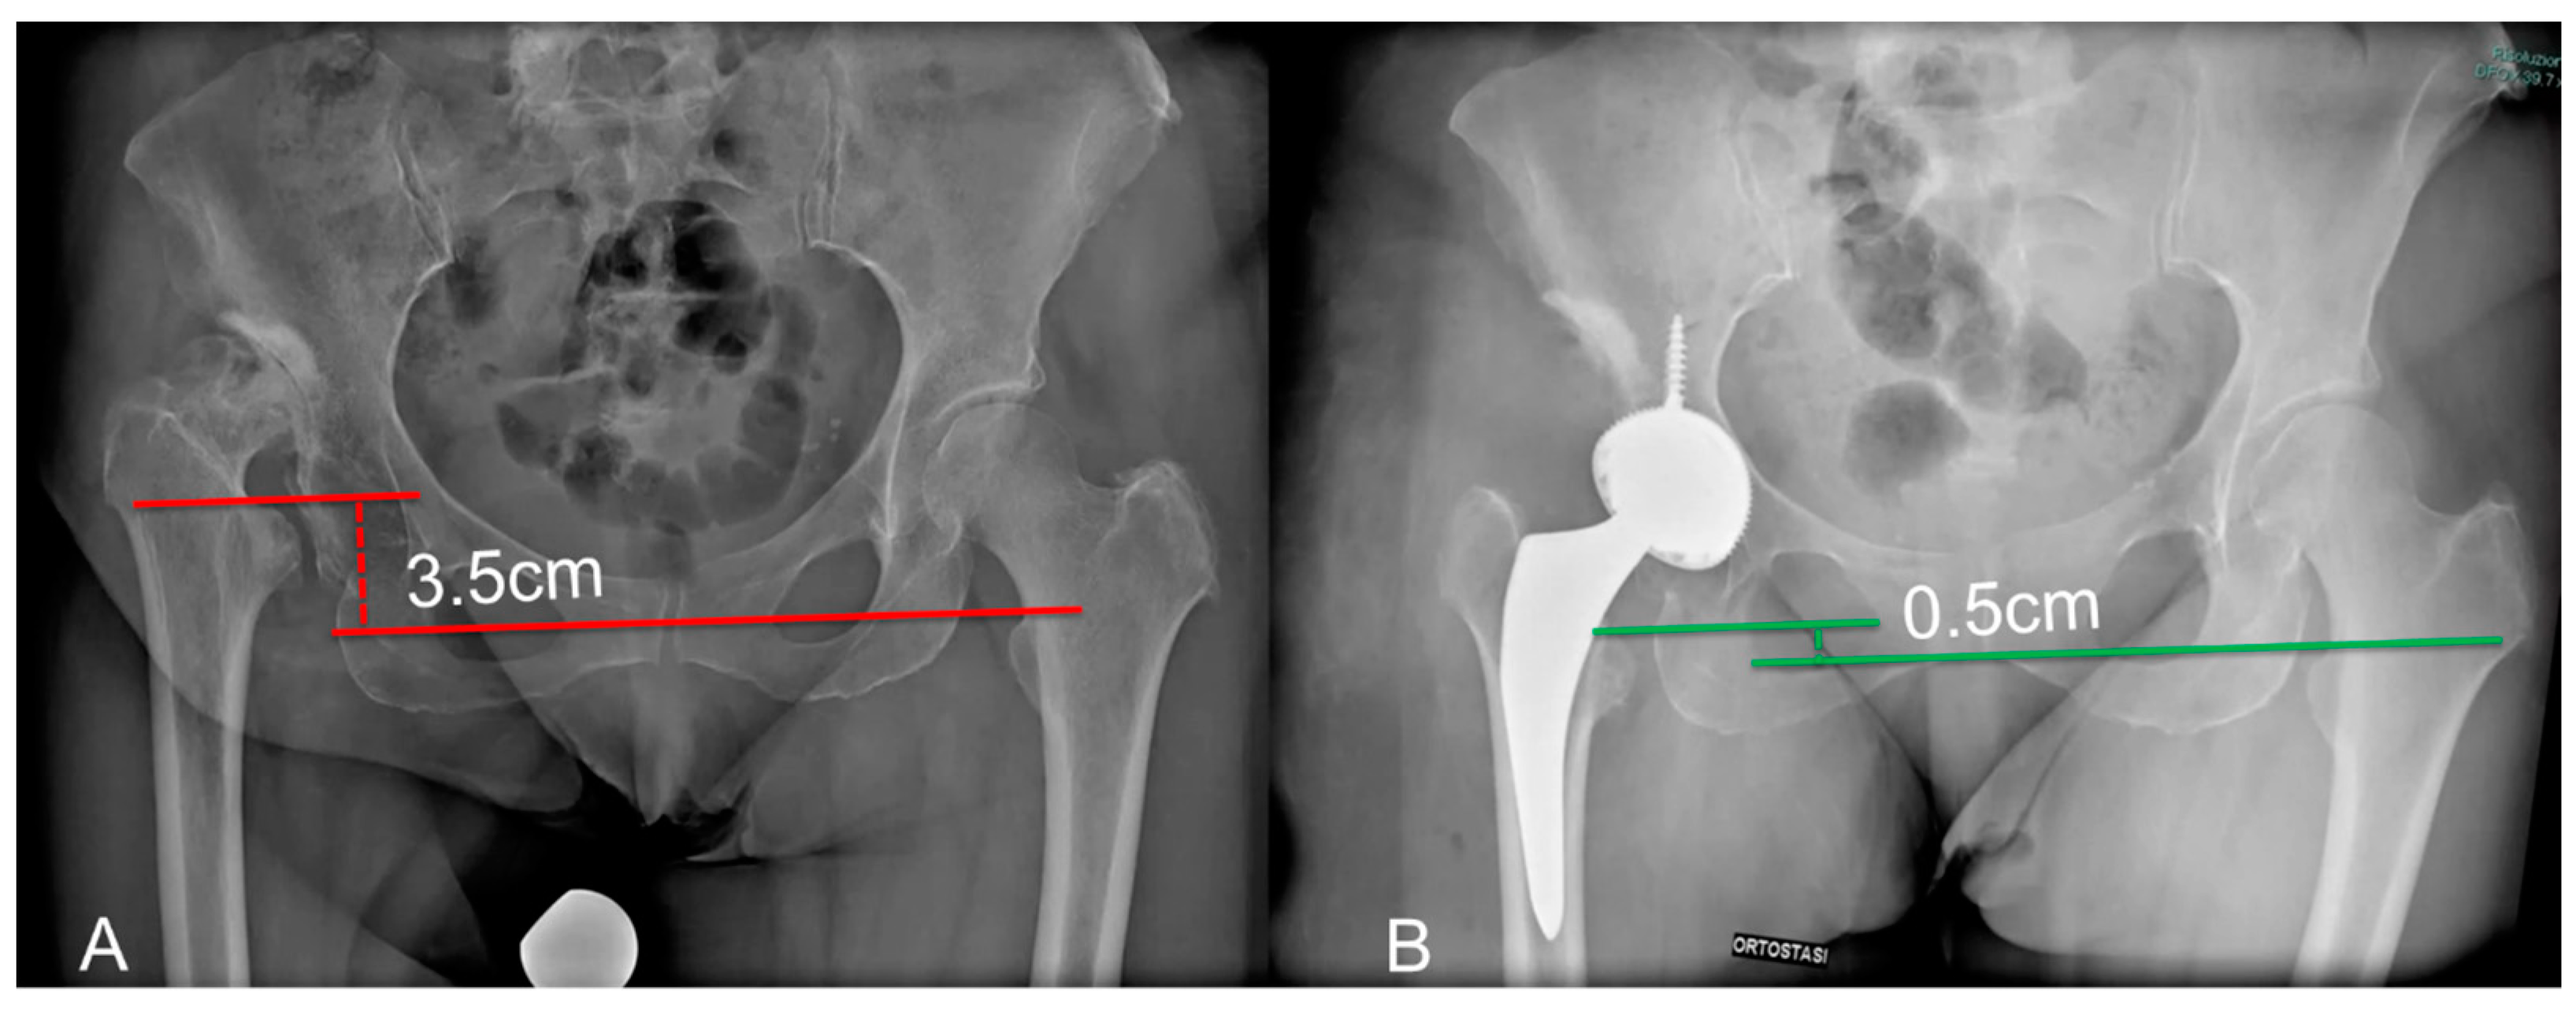

| Apparent LLD (cm) | 3.5 (2.5–4.3) | 1.2 (0.5–2.4) | <0.001 |

| True LLD (cm) | 3.4 (1.6–4) | 0.8 (0.3–1.1) | <0.0001 |